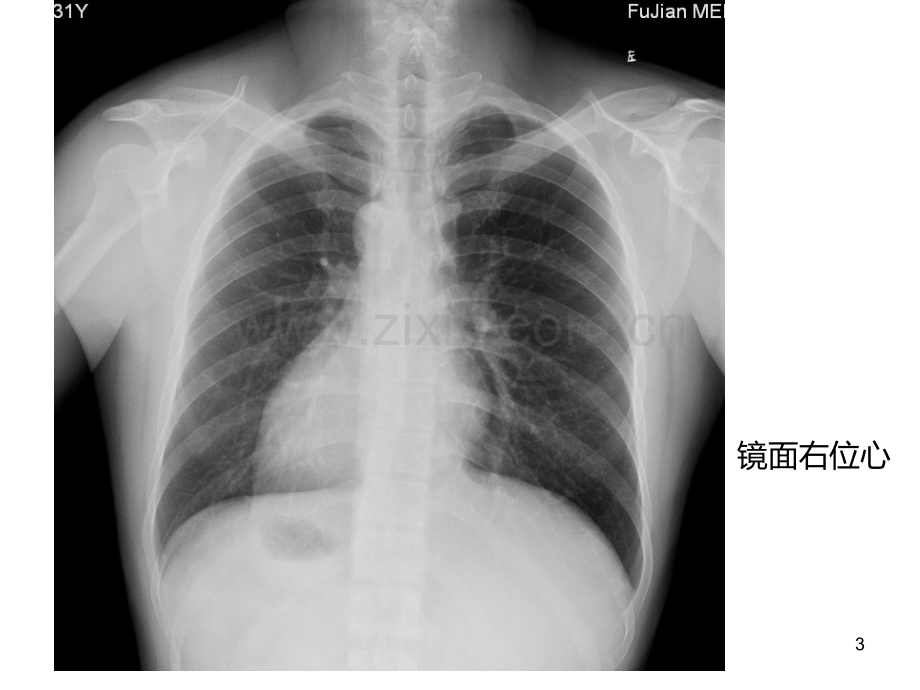

心脏大血管先天异常福建医科大学附属第一医院影像科 林娜1一、心脏位置异常镜面右位心:右位心合并内脏转位,是相对多见的先天性心脏位置异常;心尖向右,心脏2/3在右,1/3在左,心脏长轴指向右前下方,心影大部在中线右侧。左旋心:又称单发左位心,心尖指向左侧,合并完全性内脏转位或不同程度的内脏转位。右旋心:又称单发右位心,心尖指向右,通常主动脉弓及降主动脉仍在左侧,其他内脏不转位。2镜面右位心3镜面右位心4右旋心5二、主动脉畸形主动脉缩窄主动脉弓中断血管环6l主动脉缩窄主动脉弓峡部狭窄(峡部:左锁骨下动脉起点与动脉导管间的区域)临床表现:上肢血压升高,下肢血压降低。X线:3字征(主动脉弓降部呈3字样改变,上部弧形代表主动脉弓,下部弧形代表降主动脉狭窄后扩张,中间凹陷代表主动脉的缩窄)7主动脉缩窄,永存左上腔静脉1829主动脉缩窄,动脉导管未闭110211主动脉缩窄12l主动脉弓中断主动脉弓的某一段完全缺如或因极度的发育不全形成闭锁,升主动脉与降主动脉间没有直接连续,降主动脉多连接到肺动脉上。患有主动脉弓中断的新生儿若不及时手术,多于出生后一个月内死于充血性心力衰竭。三联征(Steidele复合畸形):主动脉弓中断-室间隔缺损-动脉导管未闭,这常是病人存活的重要条件。部分与拇指畸形并存成为“Halt-Oram”综合征。13根据中断的位置分三型:(据Van praagh R报道)A型,约占43%,中断位于左锁骨下动脉起始部远端;B型,约占53%,中断位于左颈总动脉与左锁骨下动脉起始部之间;C型,约占4%,中断位于头臂干与左颈总动脉起始部之间。这三种类型又可根据动脉导管的开闭,左锁骨下动脉的起始点以及中断部位的结构连续性形成若干变异。X线:缺乏特征,心影增大,主动脉结影消失,肋骨下缘切迹1415161718心脏增大,上纵隔通常较窄,主动脉结常缺如19l血管环先天性主动脉弓发育畸形,由异常持续存在的未退化的主动脉弓及其分支组成的环状结构,包绕了气管和食管,引起呼吸道和食道梗阻。包括:双主动脉弓、右位主动脉弓伴迷走左锁骨下动脉、肺动脉吊带临床症状:与气管狭窄相似,生后呼吸困难,持续喘憋,反复呼吸道感染。20双主动脉弓临床最常见的血管环形式 X线:前后位上胸椎第3、4水平上段可见食管两侧(也可以右侧为主)的锯齿状切迹,且右侧的压迹更深。在侧位和左前斜位胸片中可见一后位的较大锯齿状切迹,则是食管后主动脉弓的特征。单侧或双侧肺野过度充气(气管或支气管主干部分梗阻)212223肺动脉吊带(迷走左肺动脉)是左肺动脉异常起源于右肺动脉的后方,呈半环形跨过右主支气管向左穿行于食道前和气管后到达左肺门,常合并气管下段、右主支气管和食管不同程度的压迫。24三、右位主动脉弓它是由于左侧第四鳃动脉弓的退化而右侧第四弓的发育的结果。按降主动脉位置分型:I型,降主动脉在脊柱右侧,多伴其他先天性心脏畸形,一般对食管无推移;II型,降主动脉在脊柱左侧,将食管推向前向左。25X线:后前位显示左上无正常主动脉结,其位于右上。诊断右位降主动脉需要高千伏摄影,以观察降主动脉 位置;进一步检查靠食管吞钡。CT:主动脉弓跨右主支气管,降主动脉位于右侧胸腔内(II型)。常合并迷走左锁骨下动脉,其起始部可见血管局限性扩张,此为左侧主动脉弓的残余。主动脉弓上层面扫描自右向左可见右锁骨下动脉、右颈总动脉和左侧头臂干。常同时显示并存的右位心和内脏反位。26右位主动脉弓I型27右位主动脉弓II型28四、主动脉弓主要分支畸形迷走右锁骨下动脉右位主动脉弓伴镜面分支右位主动脉弓伴迷走左锁骨下动脉29l迷走右锁骨下动脉最常见的主动脉弓畸形,发病率约1/200主动脉弓的最后一支头臂血管发出,常起始于主动脉弓和降主动脉的连接部,成为主动脉弓的第4支头臂动脉分支从下方自左向右上行穿过后纵隔,一般在第4颈椎至第4胸椎间80%位于食管后面(在食管后壁形成一斜的螺旋状压迹),15%位于食管与气管之间,仅5%-10%位于气管前30X线:观察纵隔和食管钡餐造影食管压迹的改变CT:气管右侧类圆形结节,走行于食管后方,沿着气管的右侧向腋窝方向延伸,与其血管壁处可见到钙化MRI:横轴位及冠状位,可发现合并的其他畸形(如主动脉缩窄,此时若迷走右锁骨下动脉起自缩窄的远端,它就成为一支主要的侧支循环动脉,肋骨切迹也表现为左侧可见)31迷走右锁骨下动脉32五、肺静脉异位引流肺静脉未能直接与左心房连接,而与右心房或体静脉系统连接的先天性心血管异位肺静脉非完全性异位引流:常无明显体征,占60%-70%,指部分的肺静脉不进入左心房而引流入体循环的静脉系统,如右心房和上、下腔静脉等处。肺静脉完全性异位引流:占30%-40%,四支肺静脉分别或汇合后连接至某一体循环,不引流入左心房,导致右心房、右心室增大;分为心上型、心下型心上型可连接至左上腔静脉、冠状窦、右上腔静脉、右心房、奇静脉心下型从汇合部有一血管经食管裂孔进入腹腔,止于门静脉或其分支33完全畸形连接必须有房间交通,肺静脉血才能进入左心,代偿情况取决于流经房间交通的血量、肺血管床的情况、有无肺静脉阻塞34X线:右心房室增大,肺血多,左心不大,主动脉弓小 肺静脉通过左上腔静脉引流者使上纵隔影突出,与下方的心影构成8字形影 心下型连接静脉表现为弯刀样佂 严重肺静脉阻塞时有肺静脉高压所致的肺血再分配及间质性水肿3536373839六、腔静脉异位引流上腔静脉先天畸形永存左上腔静脉(双侧上腔静脉畸形)左颈内静脉与左锁骨下静脉汇合到永存左上腔静脉,引流入冠状静脉窦或左心房 右上腔静脉直接连至左心房很少见下腔静脉畸形:主要是与左心房连接,也常有奇静脉将部分下腔静脉血引流至上腔静脉X线:上腔静脉异位引流:在主动脉弓水平,可发现两侧上腔静脉影或右上腔静脉缺如 下腔静脉异位引流:在肾脏或肝脏水平,可发现双下腔静脉或下腔静脉中断并与奇静脉系统异常连接,奇静脉系统扩张401永存左上腔静脉41242343永存左上腔静脉144245346447548495051522024/5/7 周二53.